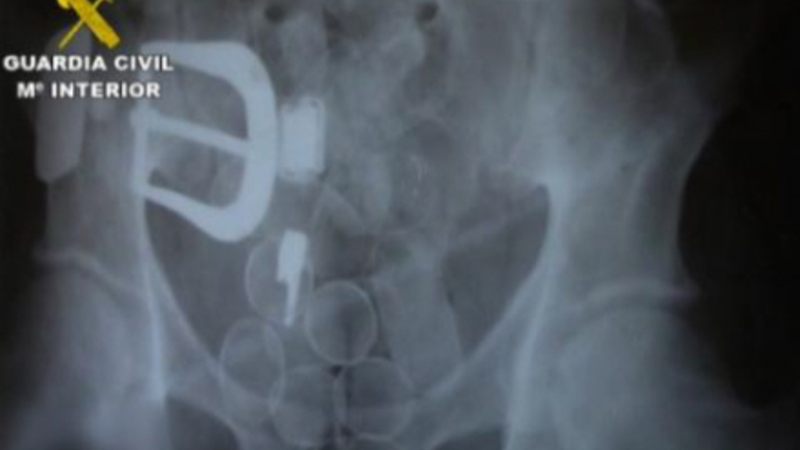

Ifølge rapporten fra Guardia Civil blev offeret, J.A.U.I., en colombiansk advokat med spansk pas, hyret af narkobagmanden fra sit hjemland til at transportere kokain i maven fra Sydamerika til Spanien.

Lige efter ankomsten til Spanien fik manden forfærdelige mavesmerter og bad sin 'arbejdsgiver', den colombianske narkobagmand J.A.V.H, om at komme på sygehus. Alt tydede på, at der var gået hul på en af pakkerne i hans mave og at han hurtigt blev forgiftet indefra. Han havde akut brug for hjælp.

Men det afviste narkobossen, der var mere bange for at miste narkoen. Han gav i stedet sit muldyr en ordentlig dosis smertestillende medicin for at milde den ulidelige smerte.

Retsmedicinere har efterfølgende slået fast, at manden døde af forgiftning, og fik skåret maven op post mortem. Narkoen var herefter blevet taget ud, og maven var igen blevet syet sammen med fiskesnor.